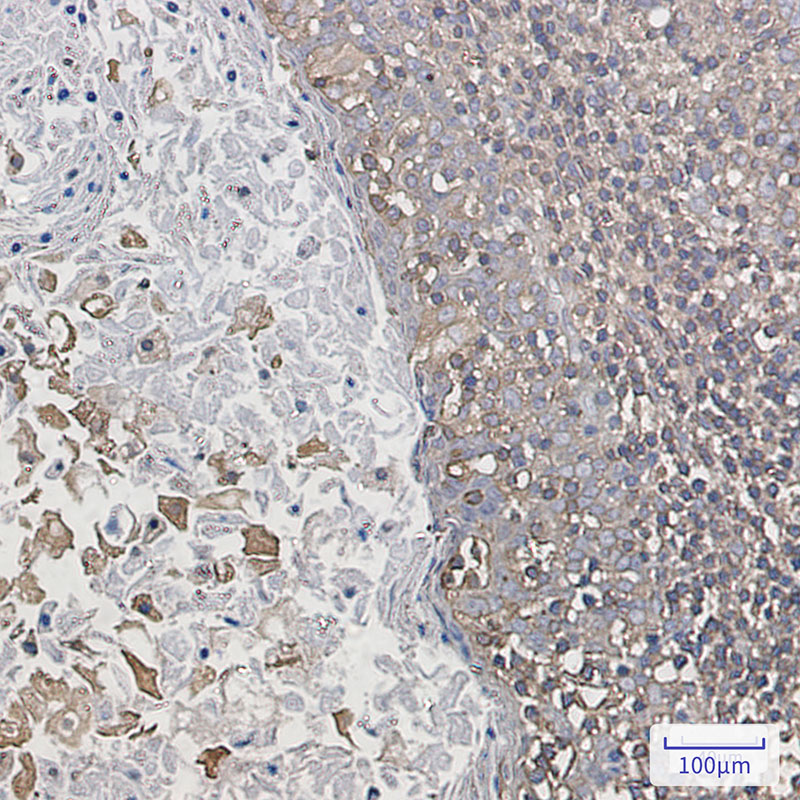

- Immunohistochemistry analysis of paraffin-embedded Human tonsil using ARPC2 antibody. High-pressure and temperature Sodium Citrate pH 6.0 was used for antigen retrieval.